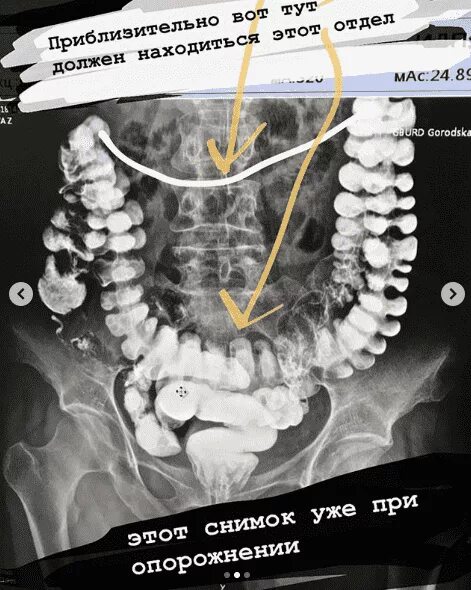

Опущение кишечника симптомы